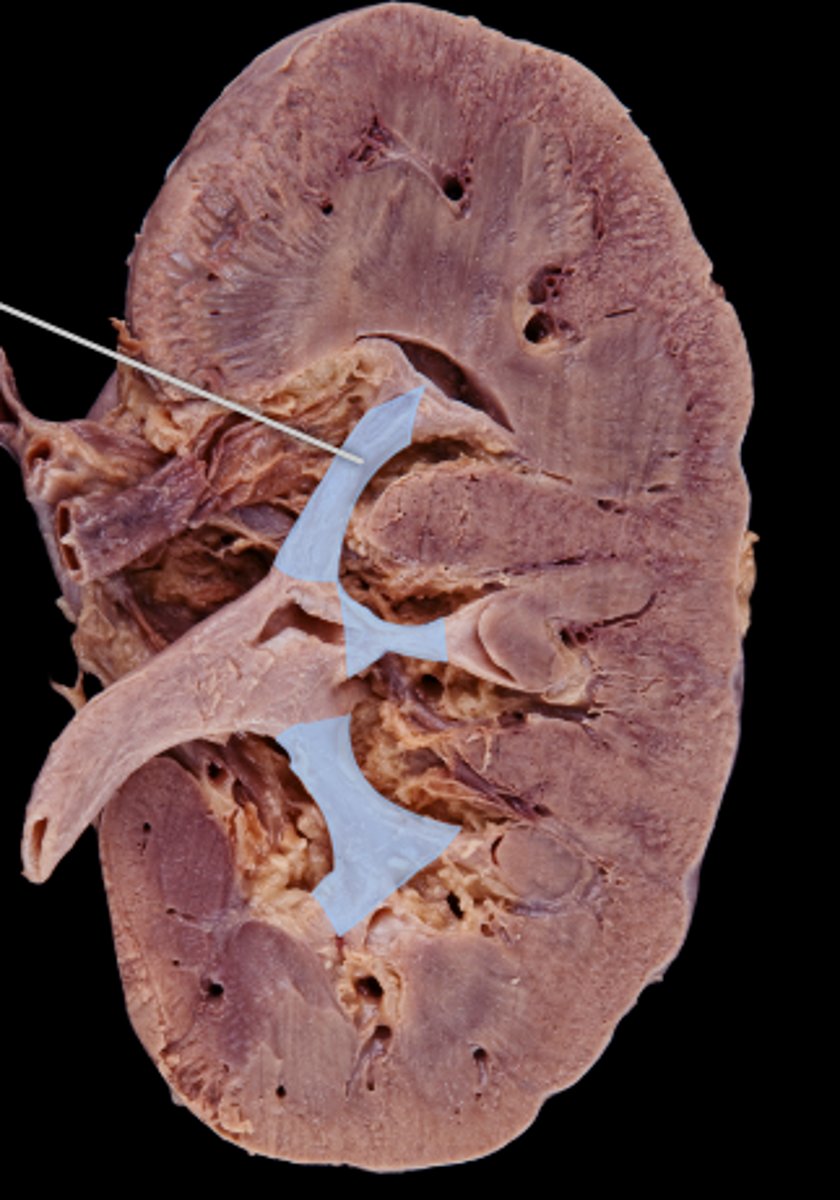

renal pyramids

striated triangular-shaped areas of tissue in the medulla of the kidney

renal papillae

medullary area of the renal pyramids where collecting ducts empty urine into the minor calyces

renal columns

extensions of cortex in between pyramids

minor calyx

cup that nestles the papilla of each pyramid; collects its urine

major calyx

urine passageway

renal pelvis

central collecting region in the kidney